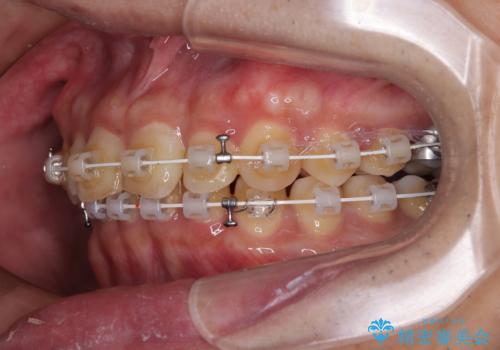

補助装置を用いて、上顎大臼歯を積極的に後方移動させながら、ディープバイトを改善していくこととしました。

強い咬合力に抵抗するため、上下ともに表側のワイヤー装置にて矯正治療を行うこととしました。